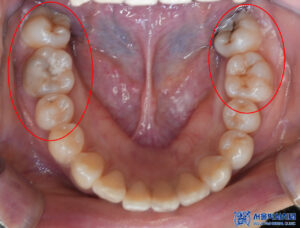

육안으로 확인해 보았을 때,

충치가 꽤나 진행되어

깊어 보이는 치아들이 많았습니다.

자세히 확인을 해보기 위해

파노라마를 촬영해 보았습니다.

파노라마 상에서도

다수 우식이 발견되었습니다.